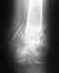

Re: оскольчатый перелом бедра со смещением

Уважаемый Александр у меня в лечении последствий травм мало опыта - поэтому нестесняясь всем задая походу интерисующие меня вопросы.

Вопрос - для чего при несращении перелома например с\3 бедренной кости синтезированного стержнем с блокированием необходимо менять стержнь на больший диаметр?